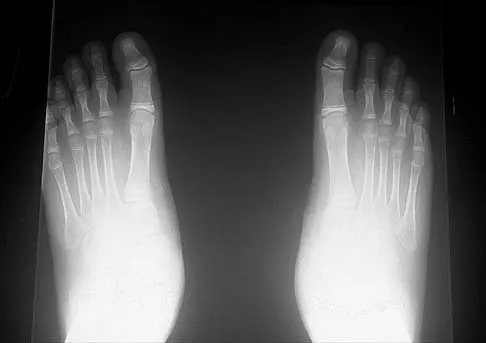

Question 44

A 21-year-old football player who sustained a direct blow to the posterior hindfoot while making a cut is unable to bear weight on the injured foot. Examination reveals tenderness and swelling of the great toe metatarsophalangeal (MTP) joint. Radiographs are shown in Figures 9a and 9b. What is the most likely diagnosis?

Explanation

Turf toe occurs in collision and contact sports in which the athlete pushes off to accelerate or change direction and there is hyperextension of the great toe MTP joint. Typically, there is also axial loading of the posterior hindfoot, which increases the hyperextension of the MTP joint. The most common presentation is pain and swelling of the MTP joint and inability to hyperextend the joint without significant symptoms. With significant force, fractures of the sesmoids and plantar soft tissues can occur. The radiographs do not show a dislocation of the great toe MTP joint because it is concentrically located on both radiographs. However, the radiographs show a fracture of the lateral sesamoid or a diastasis of a bipartite lateral sesamoid. The medial sesamoid is also proximal indicating a rupture of the plantar (volar) plate. Therefore, the most likely diagnosis is a fracture of the lateral sesamoid with rupture of the plantar plate leading to proximal migration of the proximal fragment of the lateral sesamoid and the medial sesamoid. Rodeo SA, et al: Diastasis of bipartite sesamoids of the first metatarsophalangeal joint. Foot Ankle 1993;l4:425-434.